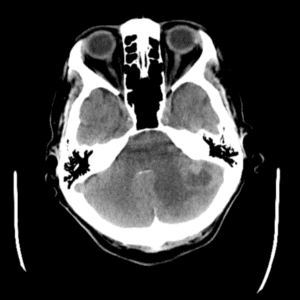

Case #7

Cerebellar metastasis